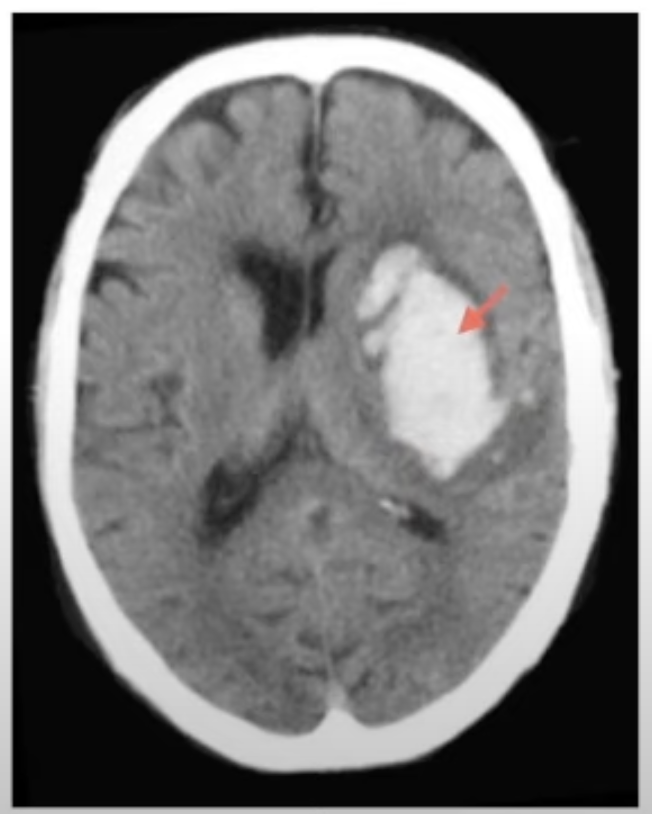

Se ve hiperdenso

A

EVC hemorrágico

GOLD STANDARD EVC Hemorrágico

TAC (blanco)